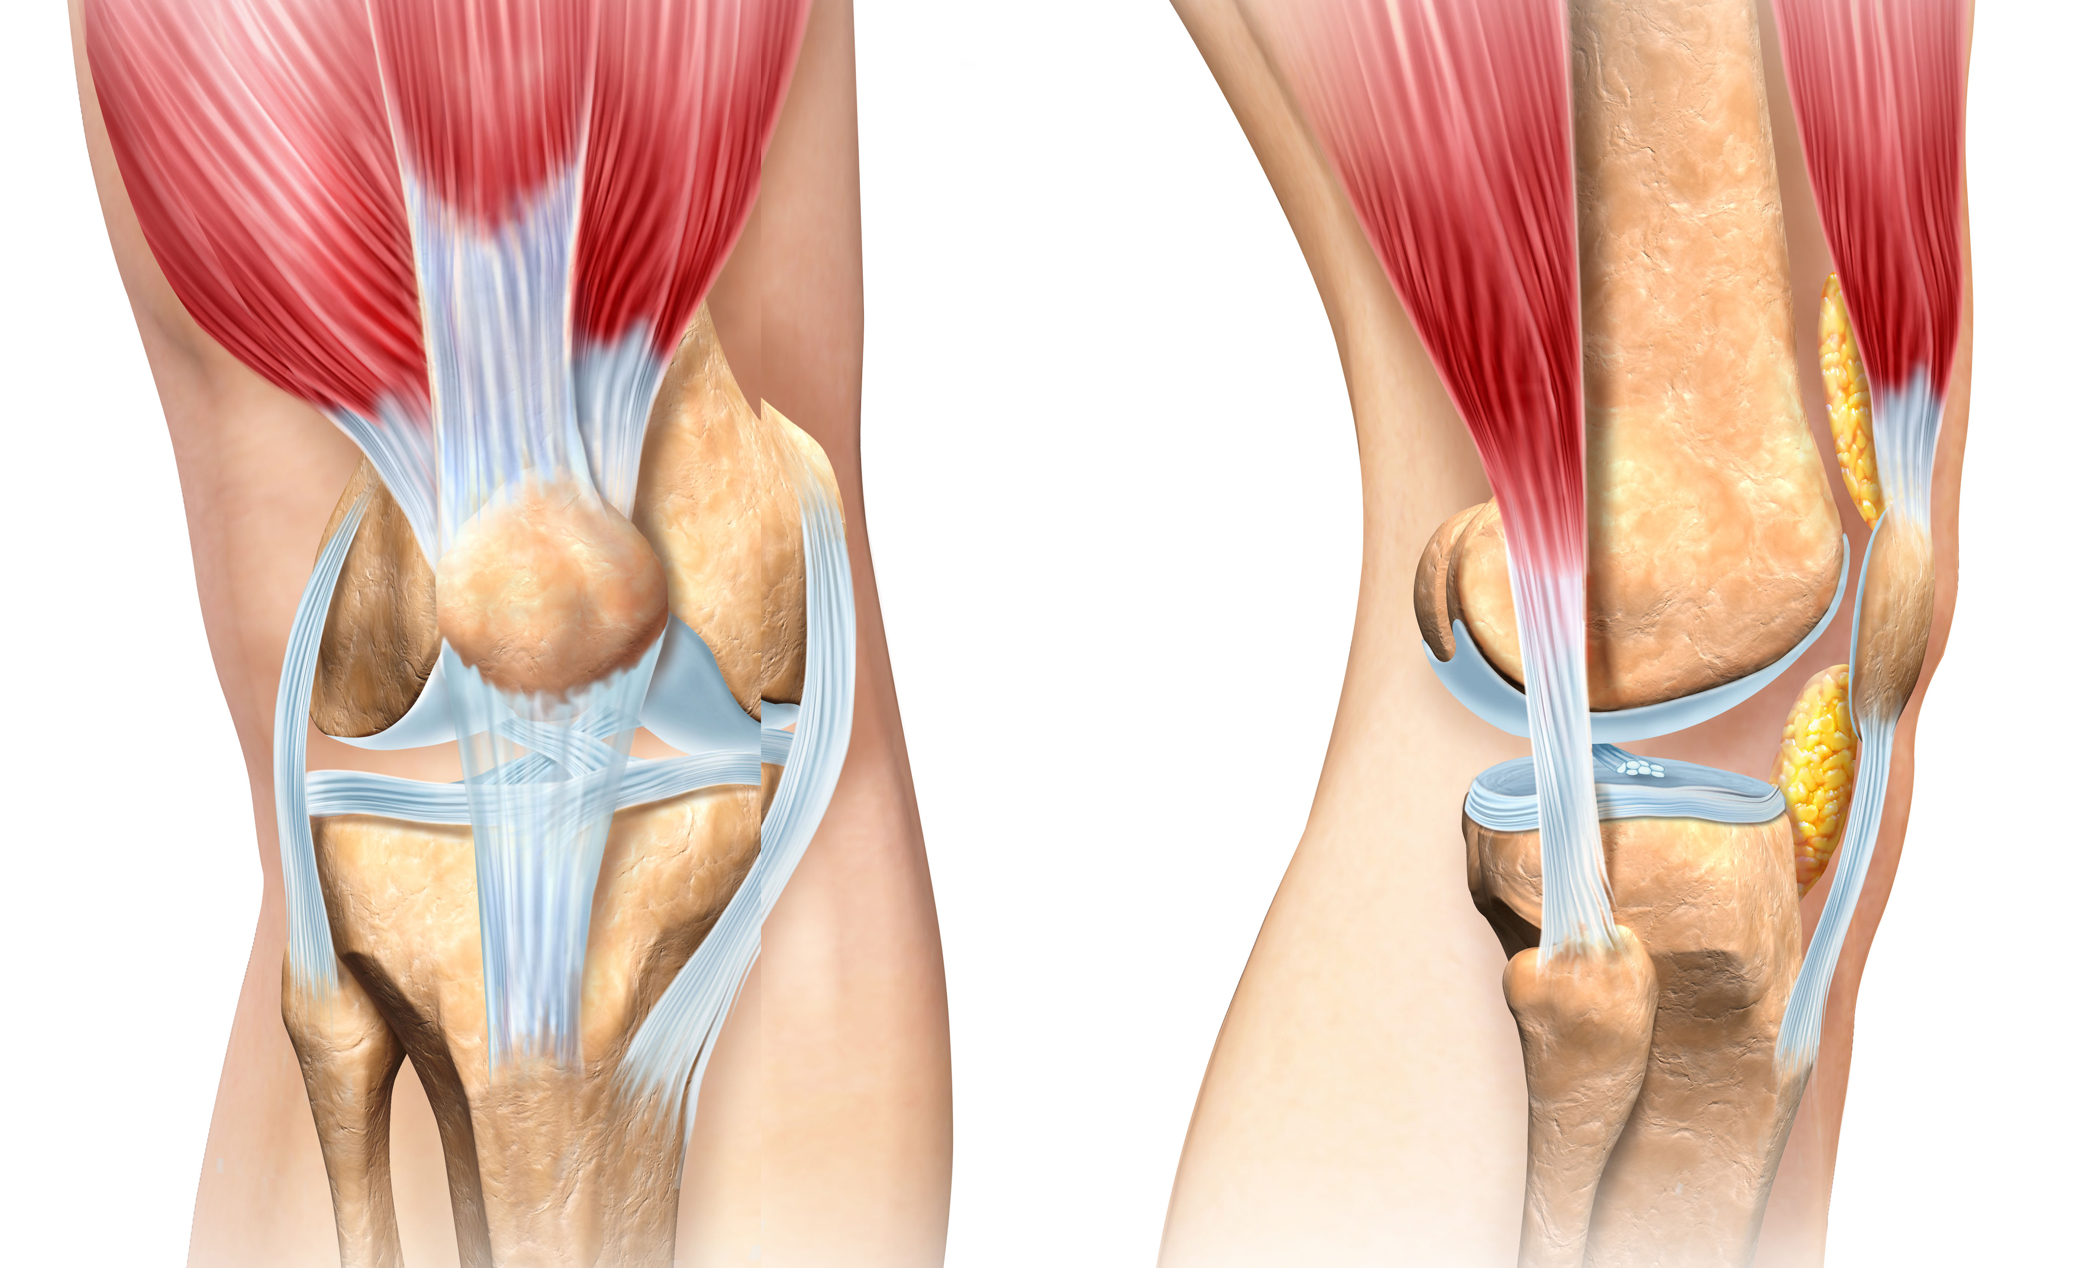

The knee is also supported by strong ligaments, which are tough bands of tissue that connect and stabilise the joint. These include the collateral ligaments on the sides of the knee and the cruciate ligaments in the centre, which control forward, backward, and rotational movements of the knee joint.

Together, these components allow the knee to function smoothly while handling the significant forces involved in movement. When any part of this system is injured or weakened – whether due to injury, arthritis, or wear and tear – it can lead to pain, swelling, or limited motion.

A decision to decrease exercise will mean a loss of muscle strength and tone around a person’s joints and an increased risk of injury. A person can end up feeling they have insufficient strength in their knee and that it is increasingly becoming unstable or might ‘give way’.